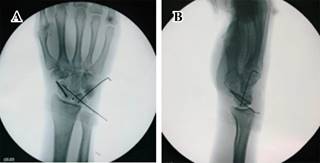

Tres días después del traumatismo, bajo anestesia general, se realiza abordaje dorsal para escafoides. Luego, bajo control fluoroscópico, se coloca clavillo Kirschner como guía. Después de corroborada adecuada colocación, se completa osteosíntesis con tornillo tipo Herbert de 2.5 mm.

Posteriormente se reconstruye ligamento escafosemilunar con ancla metálica Micro Corkscrew (Arthrex®) de 2.2 mm. Después se colocan dos clavillos Kirchner de 1.2 mm, el primero transescafo-perilunar y el segundo fijando piramidal y semilunar (Figura 4). Se realizan maniobras dinámicas posterior a la osteosíntesis, demostrando adecuada estabilidad en huesos del carpo. Se realiza cierre por planos y es inmovilizado nuevamente con férula tipo pinza de azúcar; solamente fue removido a las dos semanas para el retiro de puntos. A las seis semanas, se retiran clavillos Kirschner y se inicia fisioterapia. Se realizó seguimiento esporádico: regreso a actividades de la vida diaria a los tres meses del procedimiento, con rangos de movilidad completos y sin dolor. A 18 meses después del traumatismo, el paciente se encuentra asintomático y sin complicaciones radiológicas (Figura 5).

Figura 4: Fluoroscopía transoperatoria. A y B) Posterior a colocación de osteosíntesis del escafoides con tornillos canulados, reparación de ligamento escafosemilunar con ancla metálica y clavillos Kirschner para el reforzamiento de la plastía.